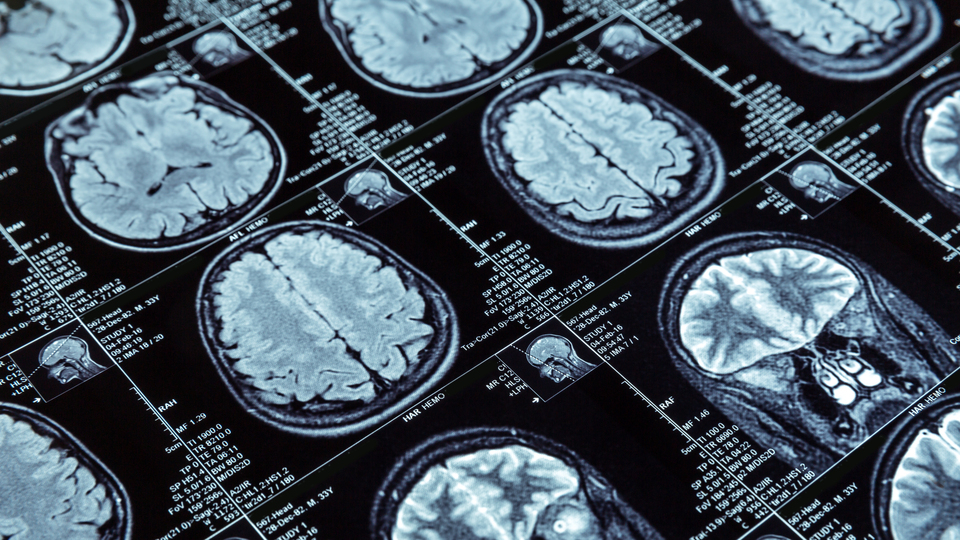

Prof. Dr. Tokçaer, Parkinson hastalığının, beyinde dopamin üreten hücrelerin hasarıyla ortaya çıkan ilerleyici bir nörolojik bozukluk olduğunu belirterek, en sık görülen belirtilerinin titreme, hareketlerde yavaşlama, kaslarda katılık, denge ve koordinasyon sorunları, yutma ve konuşma güçlükleri ile bilişsel işlevlerde azalma olduğunu kaydetti.